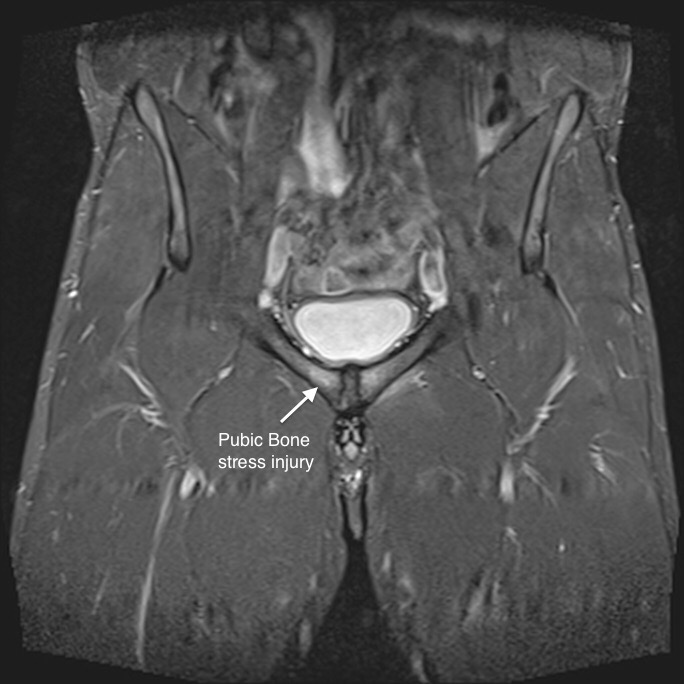

For cycling and swimming, just repeat the paragraph above. I’ve had several friends that have dealt with groin injuries that have been able to move on to other sports without problems and not have any pain or discomfort. I think the issue here is that the names sports hernia and athletic pubalgia are really bad names assigned to a plethora of injuries of the core muscles in the groin, abdomen, and back. There are a bunch of moving parts down there and a lot of different things can go wrong. Unfortunately, pills or shots don’t fix most of them so the pharmaceutical industry doesn’t pump big money into the science of these injuries. Every person’s injury can be different. While sharing experiences is certainly worthwhile (especially when there is so little good information available), it is important to get real diagnosis for the specific injury And the specific athlete.

$13,000.00 is a lot of money and insurance isn’t covering it. Or is it? You see, my employer thinks our insurance is really easy to use. It really isn’t bad coverage, it’s just confusing. I’m sure if you are based in the corporate headquarters, every provider in the region is familiar with it. But we are self-insured using a couple networks behind the scenes for pricing. And that last sentence is the key. When I call a new doctor office and they ask about insurance, I find it easier to just say I have Cigna because that is the network that our insurance uses for pricing. But that is not who provides coverage as I was reminded when I called our health plan folks last week to find out if there was anything I could do to get part of this surgery covered. I related the story and was told that as far as she knew there were no such exclusions within our plan. Marcia from Dr. Meyers’ office hadn’t called to ask about coverage of the surgery, but only to get the MRI’s approved. She had just assumed it would be Cigna’s policy. This was my fault, because I had told her I have Cigna insurance. So, the procedure and diagnosis codes, along with relevant findings from Monday have been faxed to my insurance provider. I am waiting rather impatiently to find out if I’d get some help. If I learn that they will cover out-of-network at 60/40, this becomes a much, much easier decision.

There sort of is. One thing that occurred to me is that while we ruled out the slight labrum tear in the left hip as a contributor to the groin pain, there is still some pain caused by that and it is still another injury. While on the phone with Dr. Meyers on Tuesday I asked if he felt I should do anything about that? He said it could be repaired at the same time if I wanted. Left untreated it could contribute to other problems down the road including contributing to needing hip replacement. So even though this is not a factor right now, it is another consideration. We didn’t discuss how the labrum repair might effect recovery time, etc. If I go the surgery route my decision around the labrum repair will depend on scheduling (another doctor is involved), recovery, and so forth. Also, whether insurance is paying anything will play a factor. The labrum repair is probably covered.at least partially. If the athletic pubalgia repair is not, and I get them done at the same time, things could get dicey monetarily speaking.